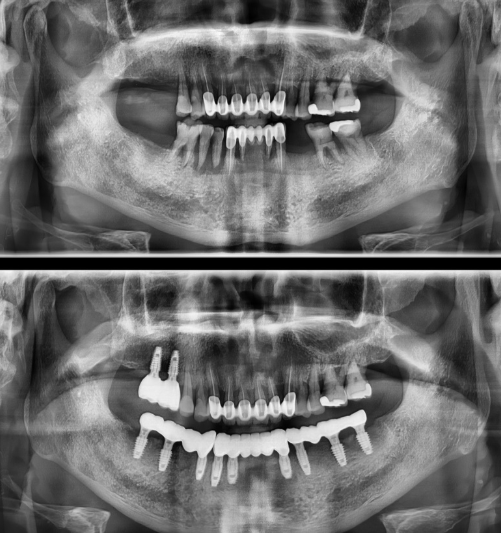

전악 임플란트

치아가 하나도 없거나 심각한 구강질환을 앓고 있어도

전악 보철을 제작, 임플란트를 치조골에 식립해

기능적, 심미적으로 자연치아와 가장 유사한 수준으로 재현이 가능합니다.